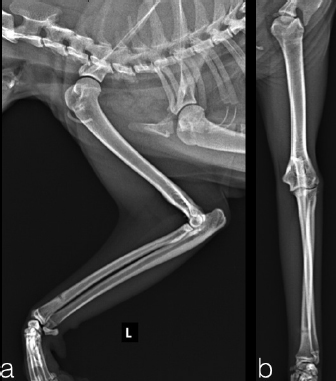

The case 1 and case 2 were evaluated every 5 days until the final evaluation at 22 and 18 days after surgery, respectively. The implants were well tolerated with acceptable three legs gait in both cats. The owners reported no management’s concern of the patient at home. At the final control, the stabilization bars were removed after clinical and radiographic evidence of joint reduction and stability. The Kirschner wires were left for further 5 days later, to be useful in case of reluxation. Protective caps and bandage were applied on the tips of Kirschner wires until their removal. Dermatitis around the pin tracts was the only minor complications associated with the transarticular external skeletal fixation, resolved after implants removal. Thirty days after surgery, in both cases, the clinical examination showed a grade 3/4° lameness (Brunnenberg, 2001), a limited range of motion (150°/70°) and a painless manipulation with no swelling visible. Mild osteoarthrosis was present at radiographic control. For both cats, physiotherapy sessions was not require; however, the owners did some home exercises like gentle passive motions, while restricted movement was continued for another 3 weeks. At 8 weeks after reduction, the cats were no longer lame and the exercise was well tolerated. The range of motion was mildly reduced without pain or joint crepitation. The radiographic follow-up at 2 months after reduction showed mild evidence of osteoarthritis (Fig. 3). The long term follow-up at 3 years assessed with a clinical examination, in both patients, showed normal function and good quality of life despite the mild reduction of the range of motion and moderate development of elbow osteoarthrisis (Fig. 4).

Fig. 4. Long-term radiographic follow-up at three years after surgery showed moderate radiographic evidence of osteoarthritis. Cranio-caudal and medio-lateral views (a-case 1 and b-case 2).

Despite the inability of the cats to load on the front limb that was fixed in flexed elbow position, the cats tolerated well the implant. Surely, the treatment with external skeletal fixation creates a sort of disadvantage for life quality, but the short period required for recovery and the speed of return to load justify the choice. The authors hypothesize that the flexible external skeletal fixation could be an options to maintain the elbow reduction and to avoid the impact of immobilization on joint health and range of motion. Postoperative recovery was managed by confining patients to prevent self-trauma and with daily skin medication around the Kirshner wire. Two months after surgery, good clinical outcome and only mild signs of osteoarthritis with marginal osteophytes can be radiographically appreciated, visible in the sagittal view in the lateral compartment. The long-term good clinical outcome, despite the development of elbow osteoarthritis, could be explained by the early treatment, closed reduction technique, the stability of the joint after fixation and the agility and lightness of the feline species. The open surgical approach and ligament reconstruction remain the gold standard in the animal with complete rupture and great elbow joint instability, however, this technique could be an alternative treatment for grade II sprain injuries of the collateral ligaments of the elbow.